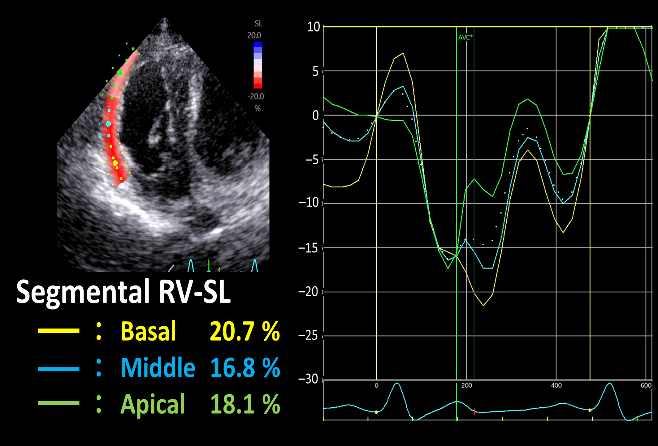

• 臨床検査に関する補助技術 (特に、腹部および心臓の超音波検査、内視鏡検査、内分泌検査など)